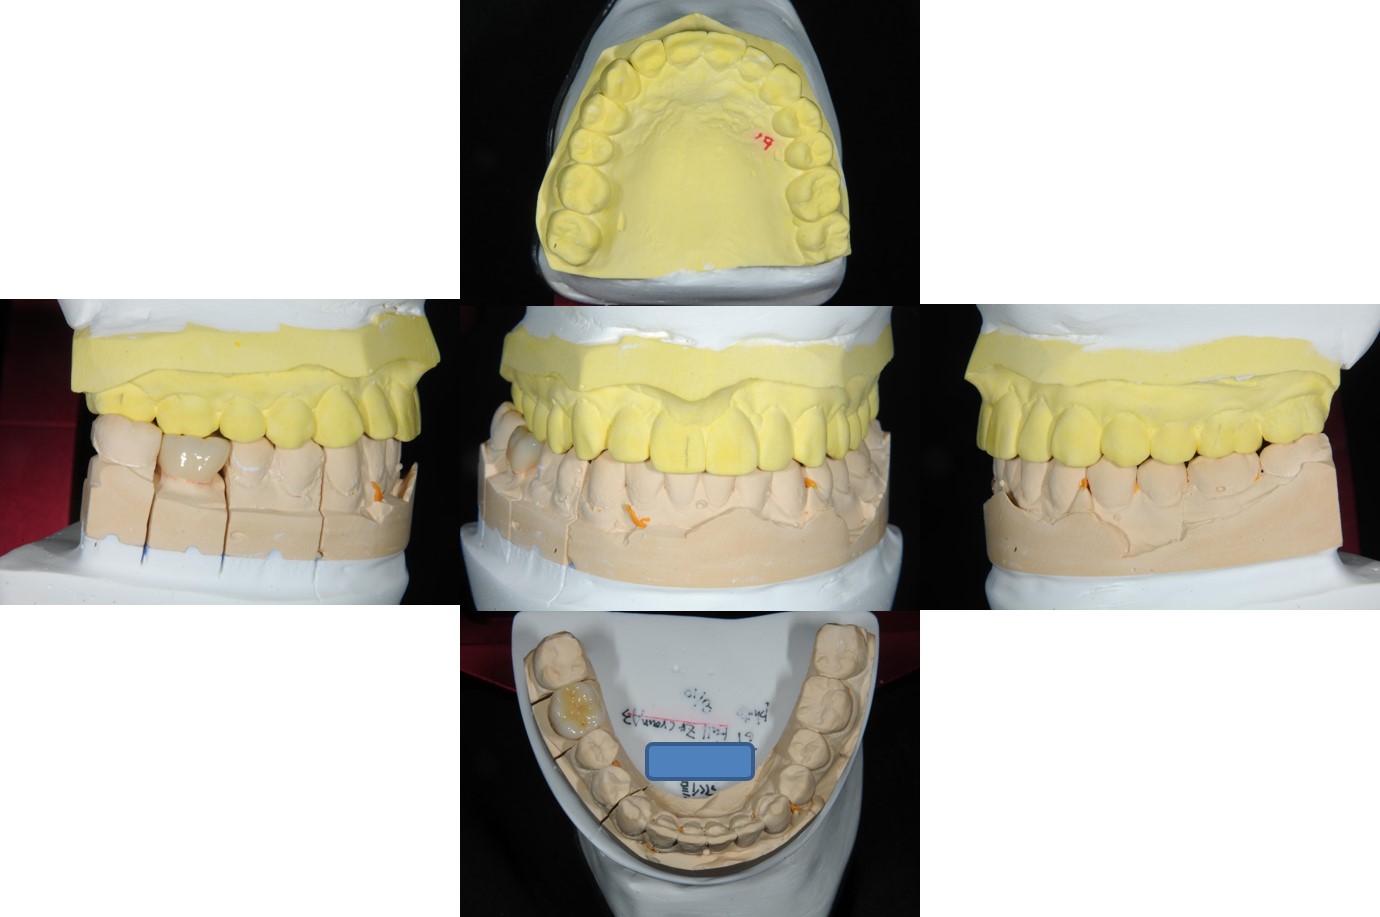

面弓轉移、上咬合器

技師於咬合器製作全瓷冠